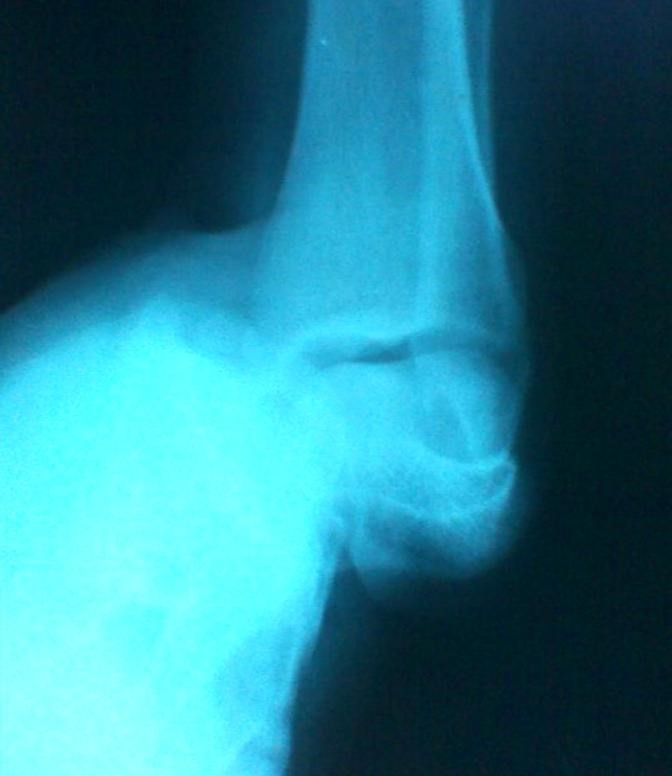

Volver a los detalles del artículo Luxación subastragalina medial